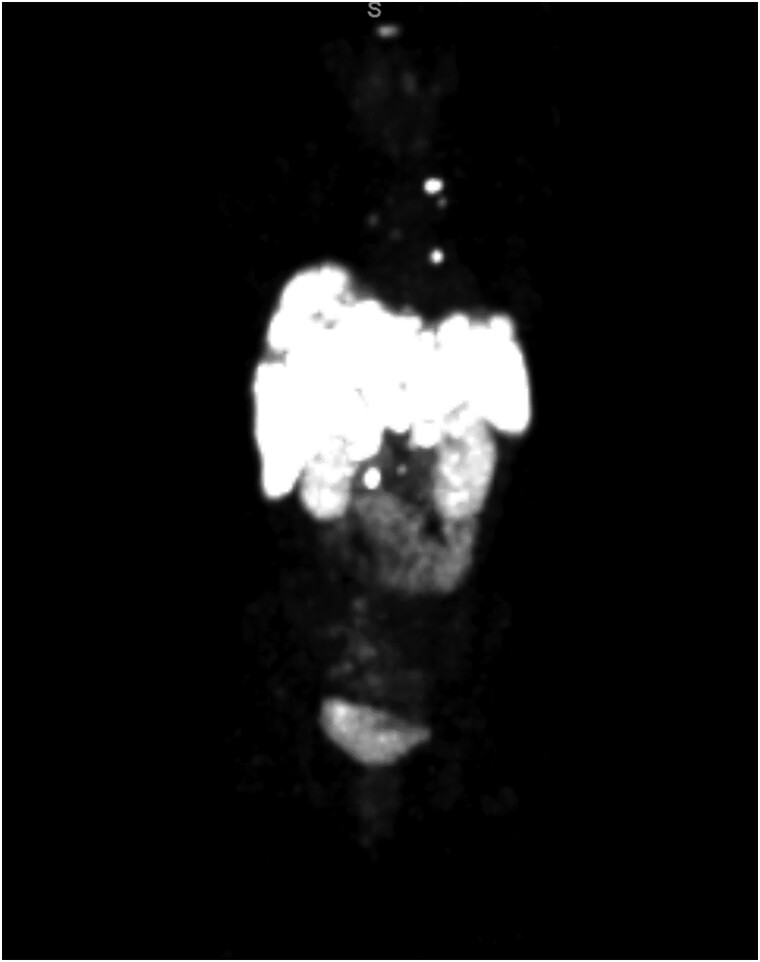

Insulinomas are rare neuroendocrine neoplasms and causes of hypoglycemia. They present with neuroglycopenic symptoms, including confusion and seizures. Suspected diagnosis must be confirmed through bloodwork and imaging. The majority of insulinomas are benign and cured surgically; less than 10% of insulinomas are malignant. Malignant insulinomas present a unique and rare challenge in managing persistent hypoglycemia and tumor burden. We present a case of a young woman who presented with Whipple triad and high-grade masses in her pancreas, liver, and distant lymph node metastases on imaging. Insulinoma was diagnosed. Hypoglycemia was managed with continuous dextrose infusion, diazoxide, and lanreotide. She was discharged on medical management and a continuous glucose monitor. Her metastatic disease is being treated with a capecitabine and temozolomide (CAPTEM) regimen showing 30% reduction in tumor burden. In conjunction with the National Institutes of Health, she is undergoing evaluation with numerous neuroendocrine tumor surgeons for cytoreductive surgery.